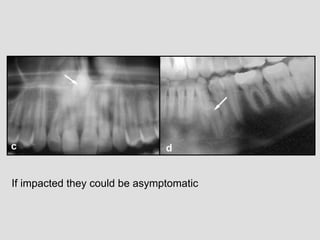

If impacted they could be asymptomatic

Supernumerary teeth could

cause many prblem as

obstructing the path of eruption

of some permanent teeth like in

this example